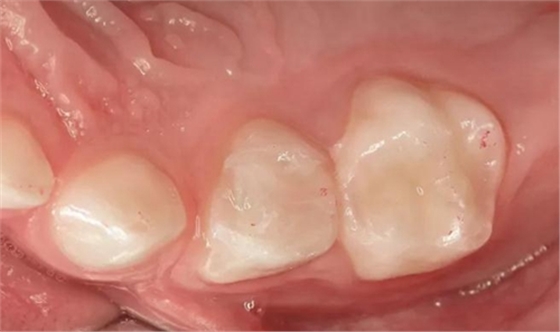

圖9:用大塊充填樹脂(x-trafil, VOCO)充填54號乳牙